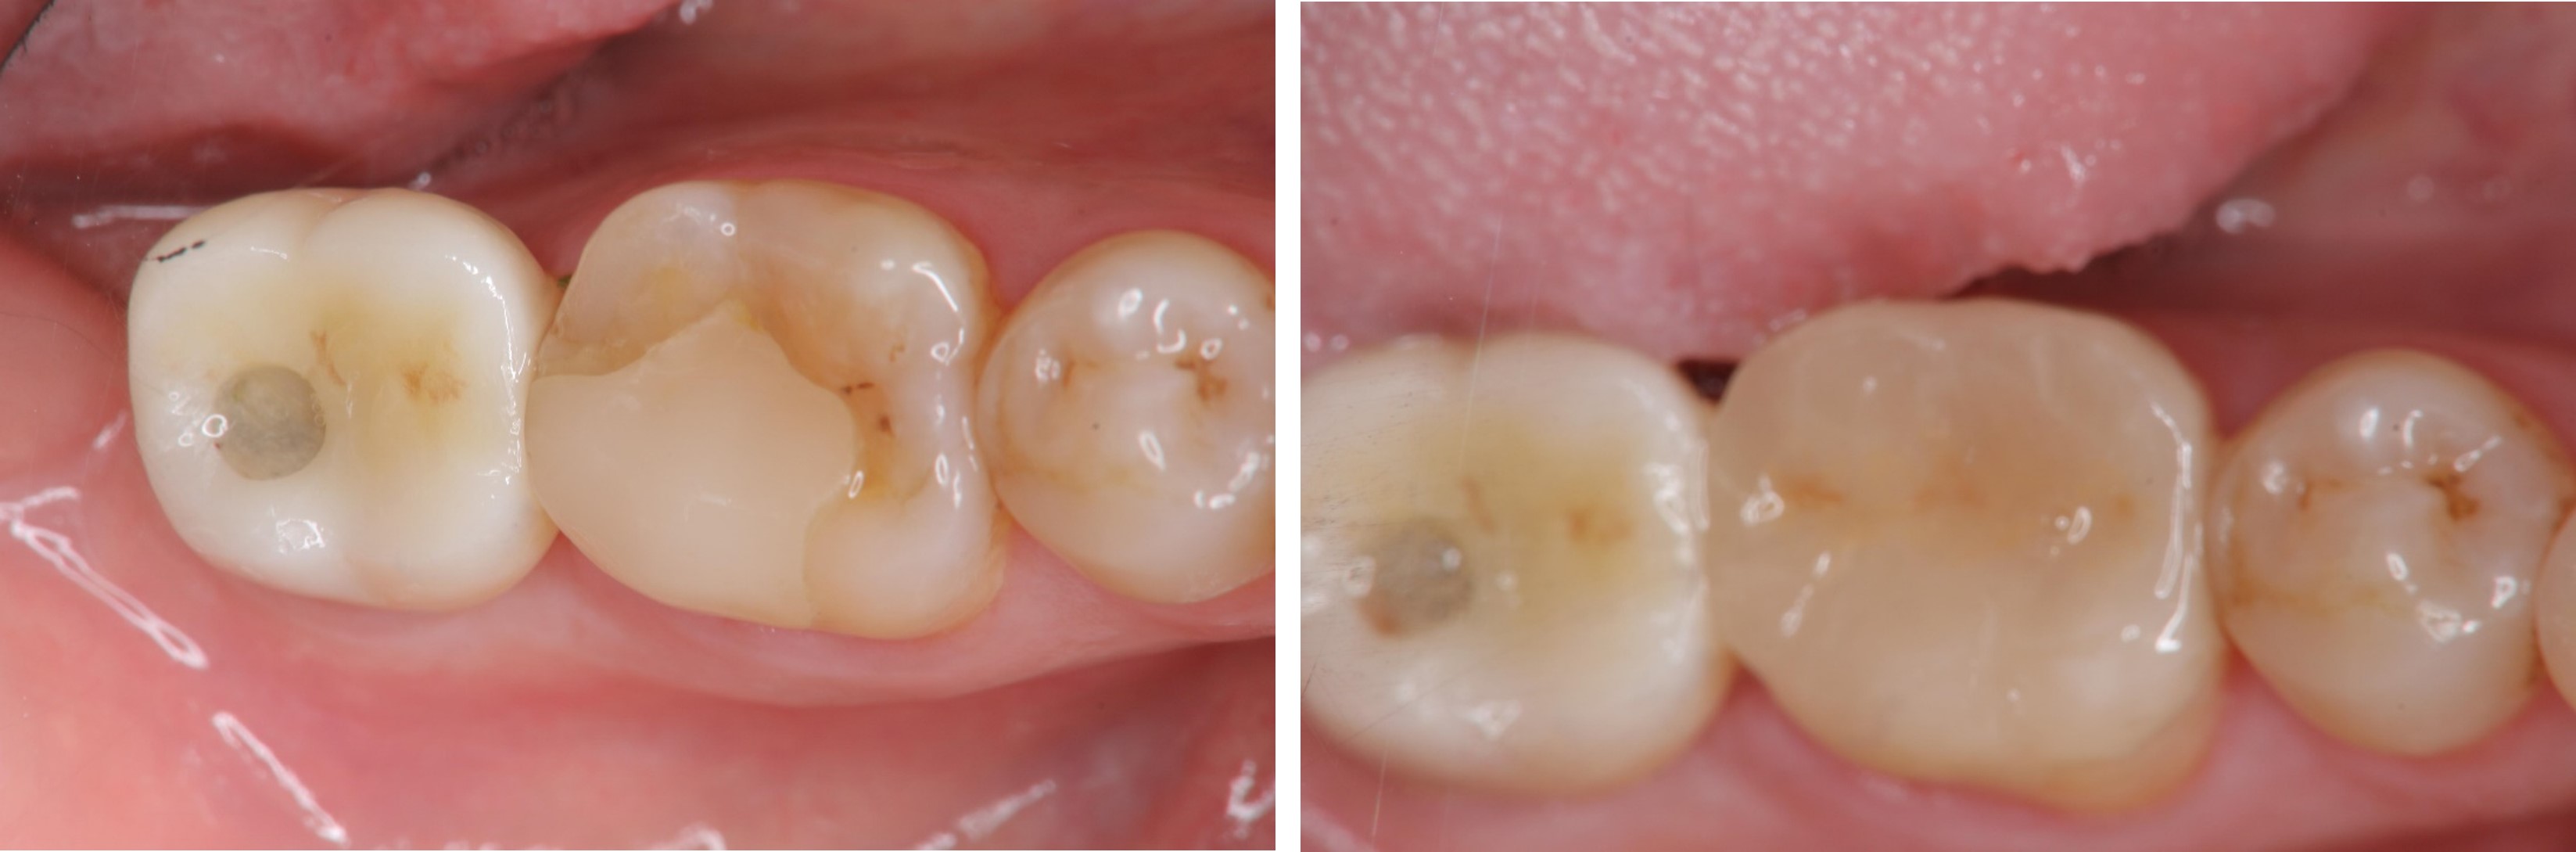

陶瓷冠塊體

貼面邊緣完整

無殘膠存在

術前、術後比較